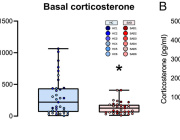

Here, we developed a method of predicting biological age of the host based on the microbiological profiles of gut microbiota using a curated dataset of 1,165 healthy individuals (3,663 microbiome samples).

Our predictive model, a human microbiome clock, has an architecture of a deep neural network and achieves the accuracy of 3.94 years mean absolute error in cross-validation.

This approach has allowed us to define two lists of 95 intestinal biomarkers of human aging. We further show that this list can be reduced to 39 taxa that convey the most information on their host’s aging.